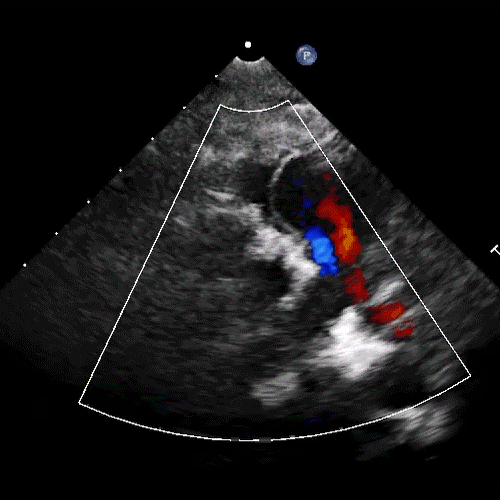

本例手术步骤:肺动脉根部离断肺动脉后,缝闭肺动脉近端。右心室无冠区做T形切口,经右心室切口,扩大室间隔缺损,缝合牛心包补片修建左室至主动脉的心内隧道。左心耳上缘与肺动脉切口下缘吻合,左心耳下缘缝合于右室切口上缘,形成肺动脉主干后壁,测量约18-20mm宽。取22#流出道单瓣补片,裁剪至合适大小,缝合至形成的肺动脉主干及右室流出道前壁,完成右室流出道及肺动脉重建。手术过程顺利,单瓣植入位置理想,术后超声见瓣叶开合正常,压差均在理想范围内,瓣膜微量返流。术中及术后患者生命体征平稳,无并发症发生。

单瓣补片重建肺动脉前壁 术后超声